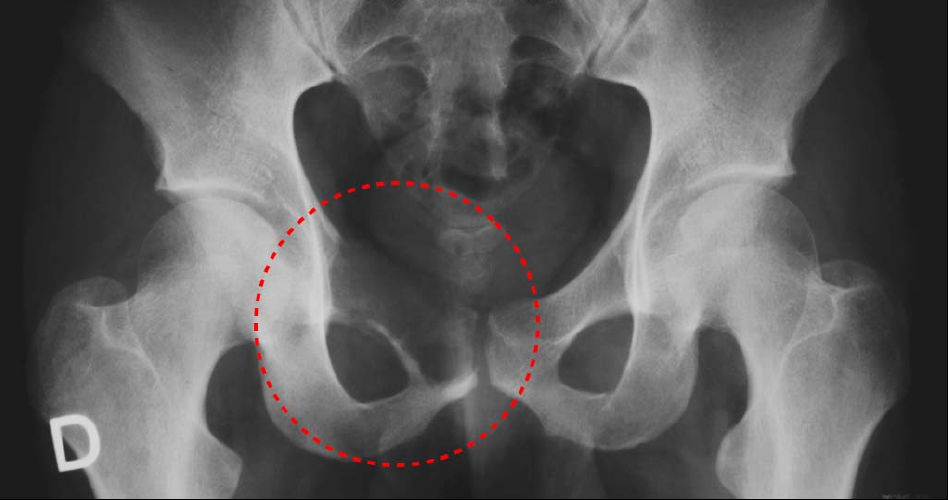

Figure2